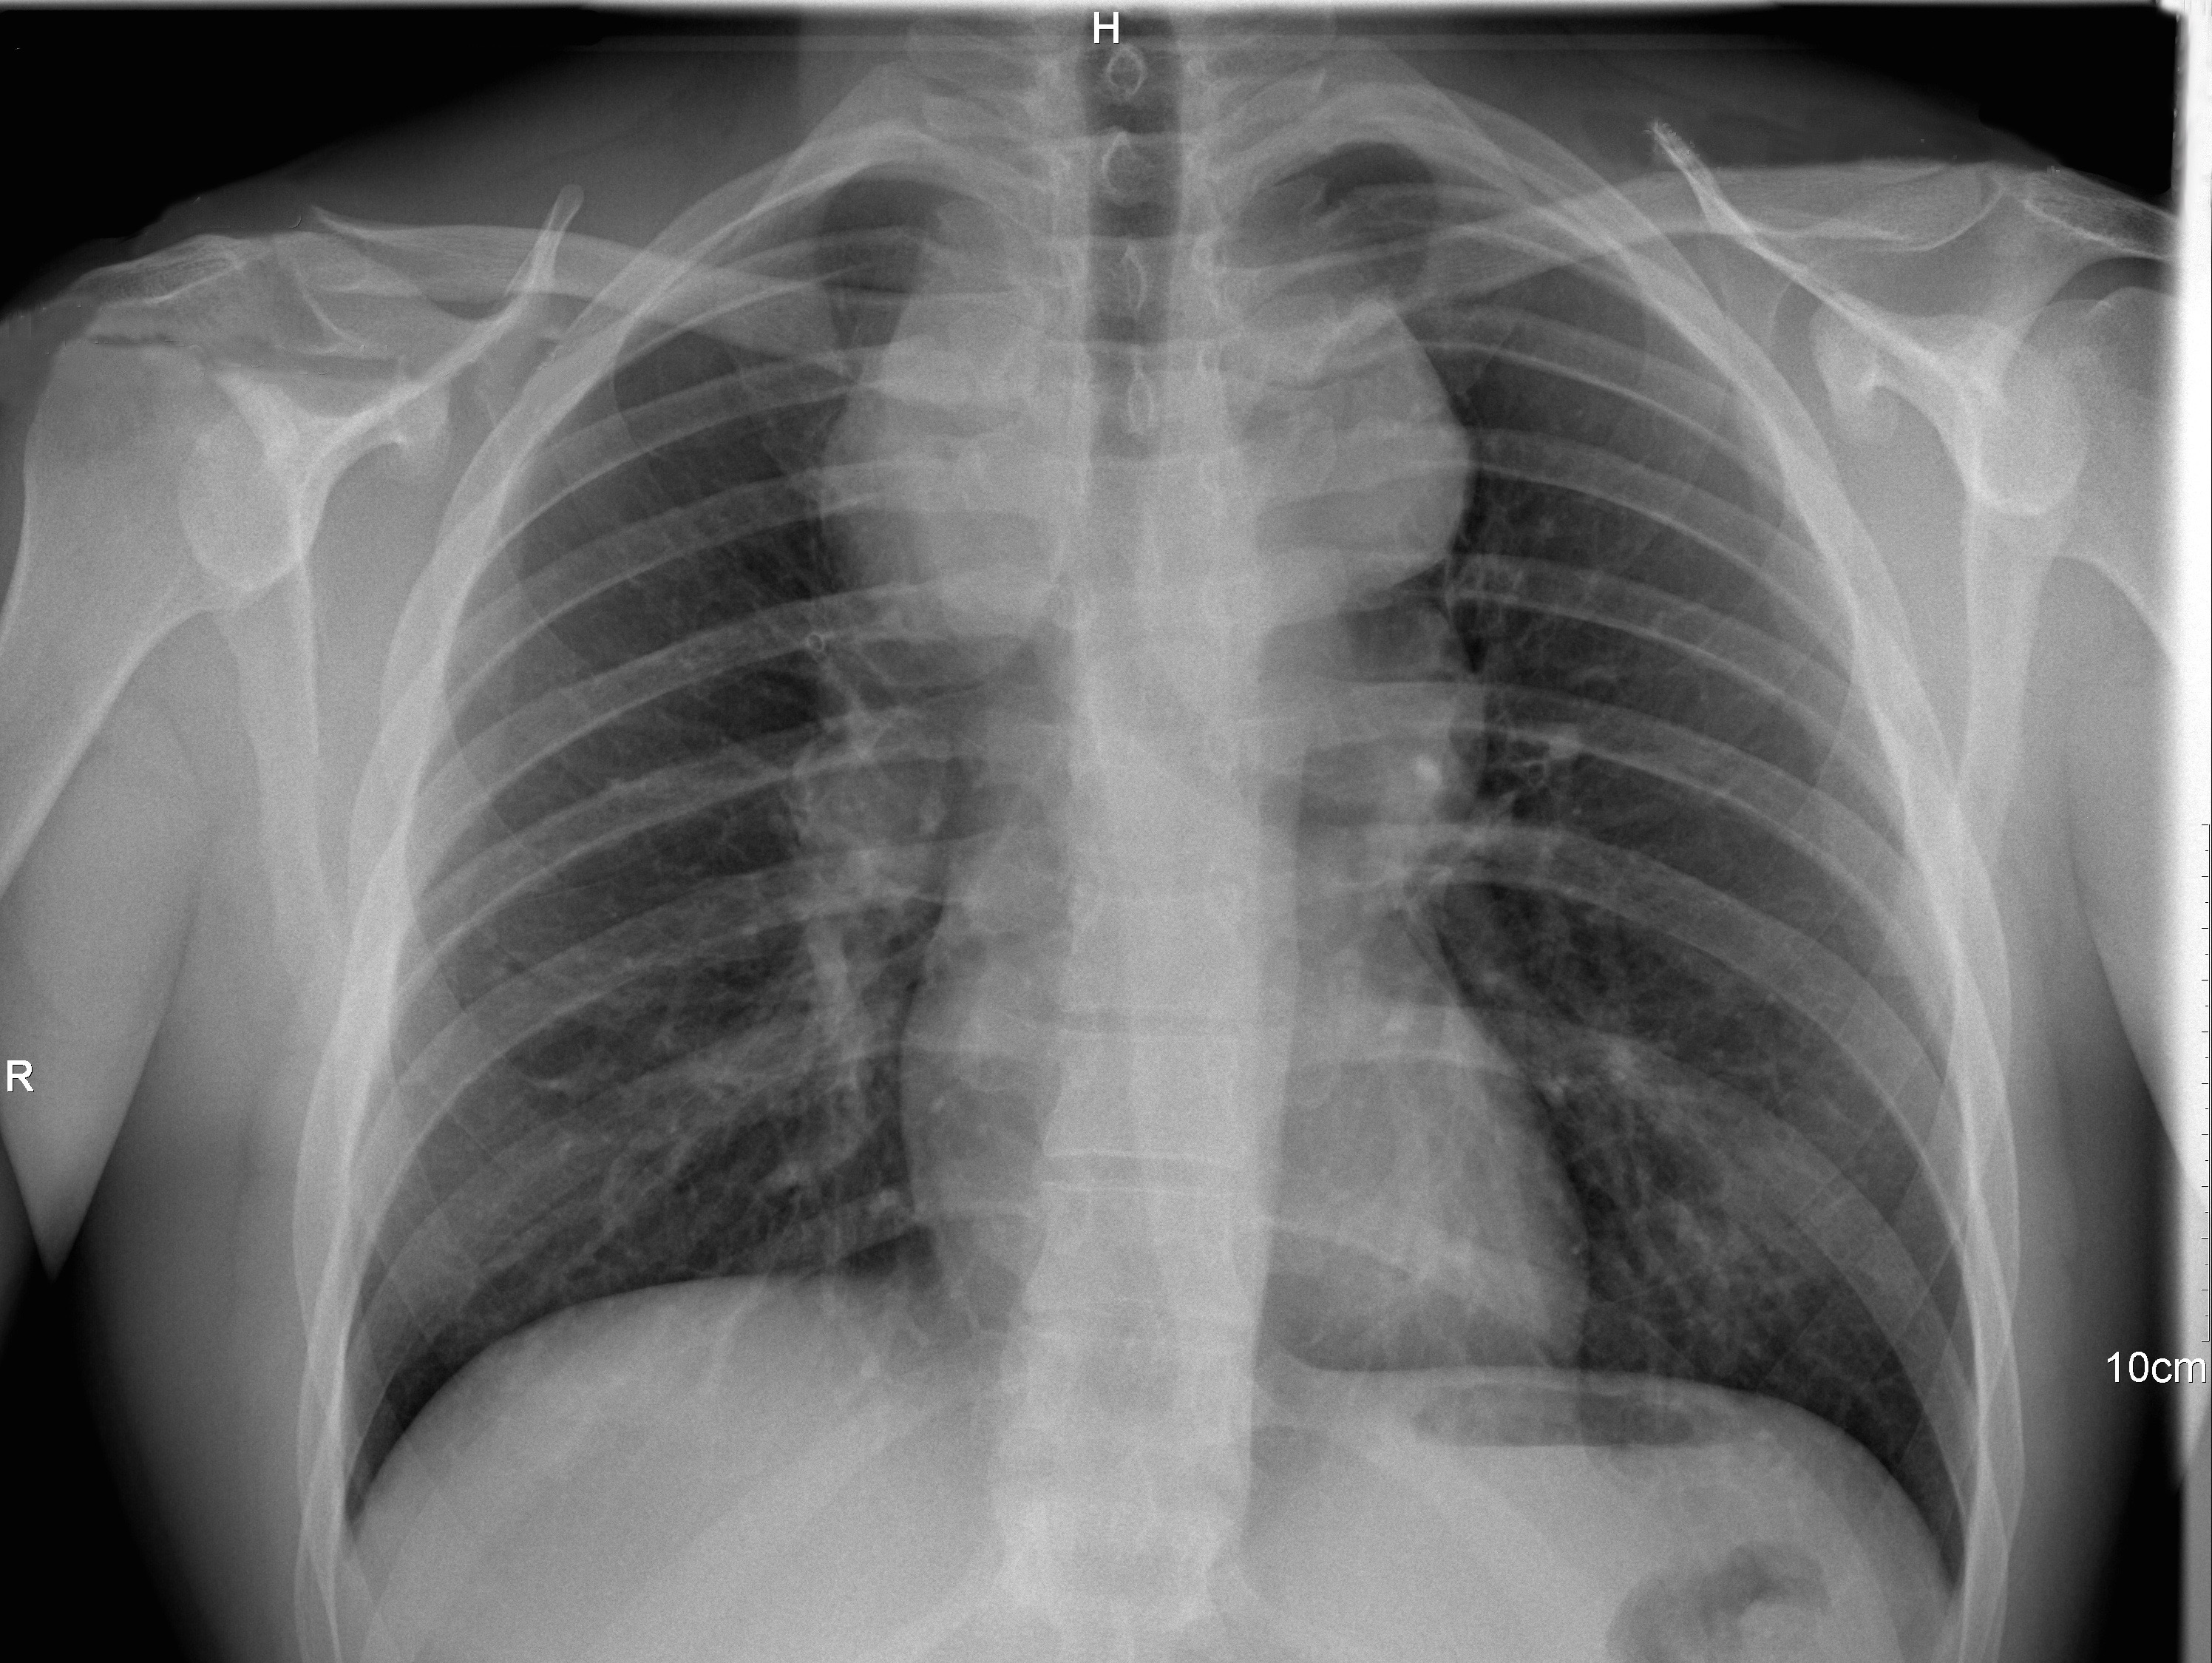

Se utiliza la radiografía simple de tórax que es la técnica de elección en estos casos porque se trata de una prueba rápida, sencilla y muy accesible, que expone al paciente a una dosis minima de radiación (en comparación con la TAC).